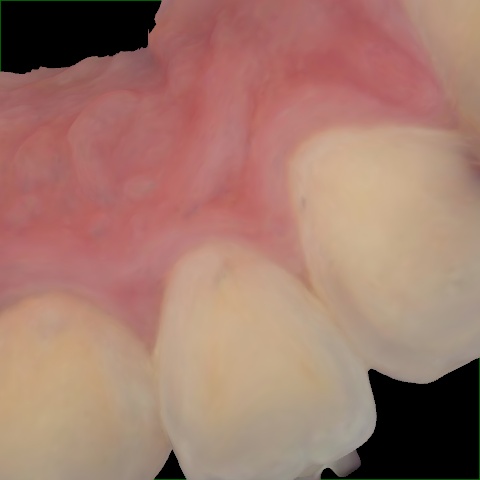

Incorrect Quality Level

The reference annotation for this image is

None

.

Please select the correct quality level.

Annotated as "Good"